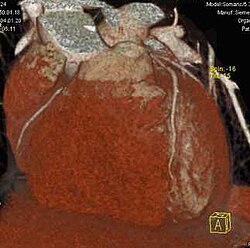

Erst mit der Einführung von Mehrzeilen-Spiral-CTs Mitte der 1990er Jahre gab es in der Computertomographie isotrope Voxel.[1] Da alle heutigen (2011) klinischen CTs kleine isotrope Voxel erzeugen können, ist eine hohe räumliche Auflösung in beliebigen Raumrichtungen möglich. Durch die multiplanare Reformation werden auch sagittale und koronale Darstellungen in hoher Qualität möglich, die für den Nicht-Radiologen erheblich einfacher zu verstehen sind. Die Maximum Intensitäts Projektion stellt die Maximalwerte aus einem frei wählbaren Datenvolumen dar, die auf eine Ebene projiziert werden, vergleichbar einem Schattenbild. Durch die heute auf Auswerte- bzw. PACS-Workstations preiswert verfügbare Rechenleistung können aus den Daten auch hochwertige 3D-Darstellungen in Form von MIP, Surface-Rendering oder – am aufwändigsten und beeindruckendsten – Raycasting erzeugt werden.

Für den Radiologen in der klinischen Routine ist die MIP zur Gefäßdarstellung und der Suche nach Lungenmetastasen sehr hilfreich. Eine 3D-Darstellung ist zur präoperativen Darstellung von Mehrfragment-Frakturen für den Chirurgen nützlich. Raytracing und MIP werden ferner im Rahmen von Spezialanwendungen für Visualisierungen in der Computertomographie des Herzens und der virtuellen Koloskopie verwendet.